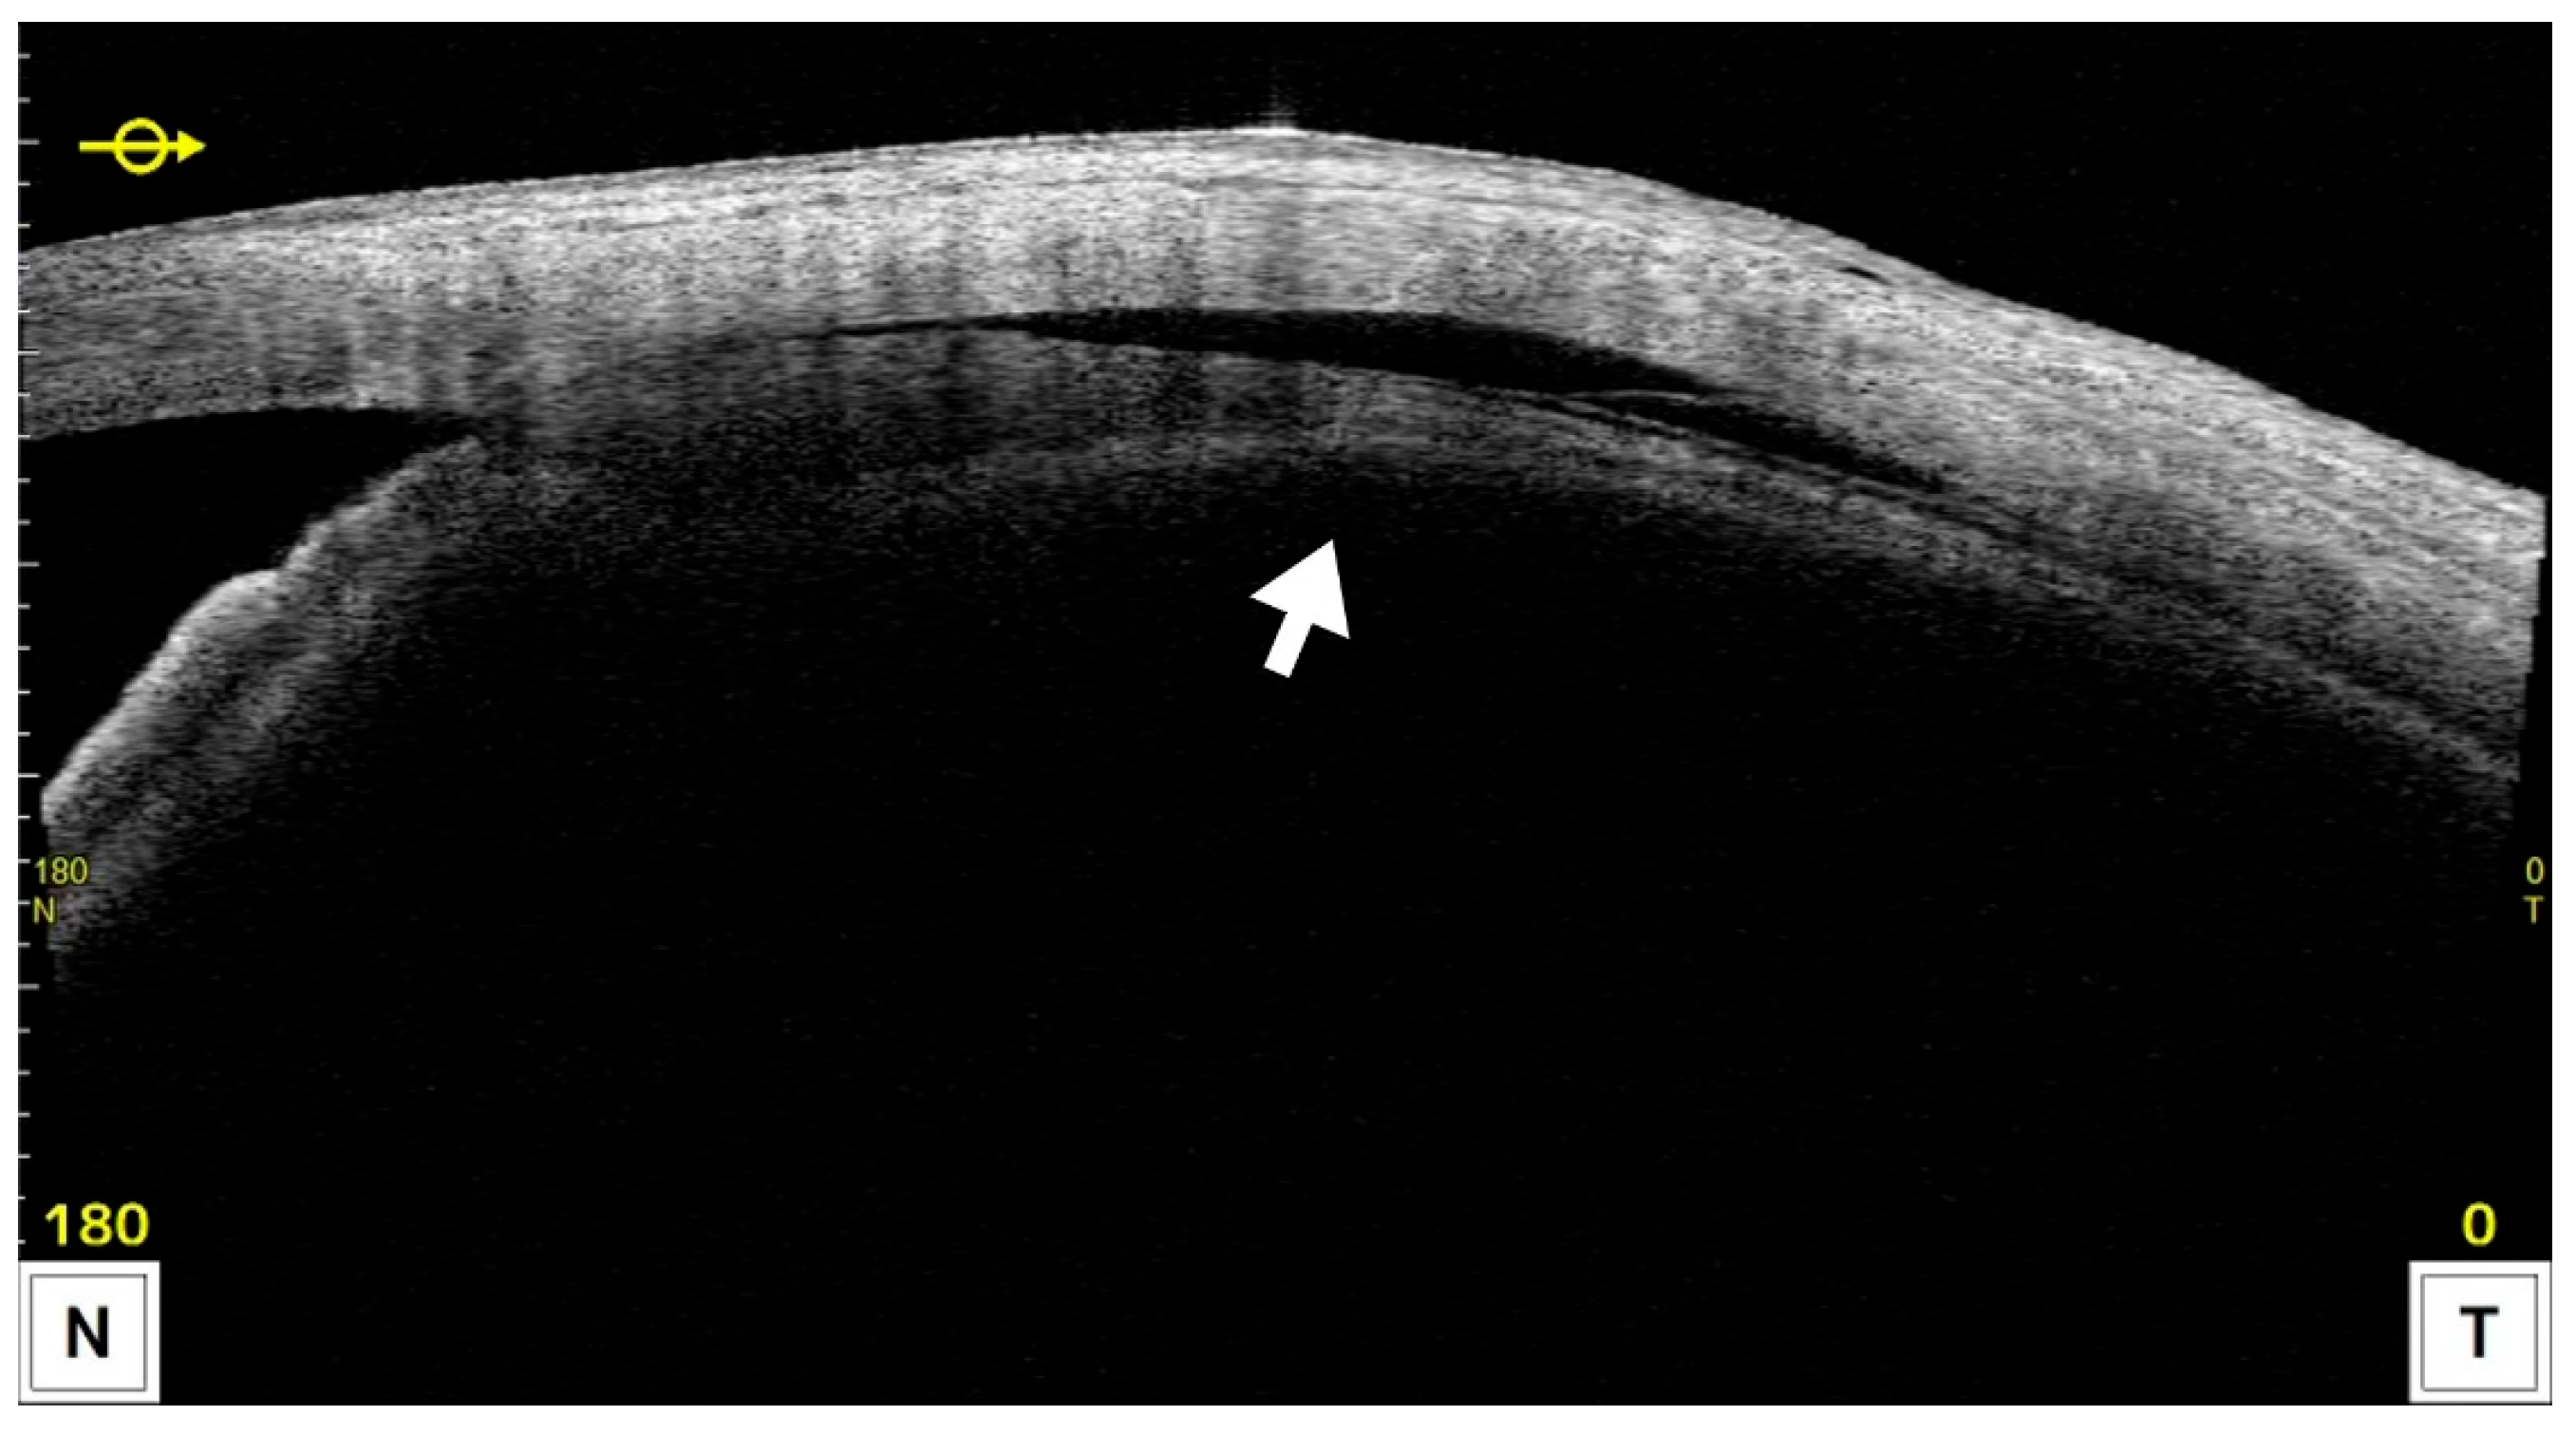

CE was detected by AS-OCT (Figure 4) in 22 eyes (59.4%) at 1 week and had resolved in all cases by 1 month postoperatively, except for one eye that developed phthisis bulbi; thereafter, IOP in the CE-positive group tended to increase. In most CE(+) cases, CE was observed in one or two quadrants at 1 week postoperatively; however, in the case that developed phthisis bulbi, marked CE was present in all four quadrants even at 3 months after MP-TSCPC. Both groups showed significant IOP reductions from baseline at all postoperative time points (p < 0.05). In the CE(+) group, IOP decreased from 20.7 ± 5.8 mmHg preoperatively to 10.0–13.4 mmHg during follow-up (31–49% reduction). In the CE(−) group, IOP decreased from 25.8 ± 7.8 mmHg to 16.8–20.6 mmHg (18–29% reduction). Between-group comparisons showed significantly lower IOP in the CE(+) group at baseline and at 1 week, 1 month, and 6 months (Figure 5), while the reduction rates were significantly greater in the CE(+) group at 1 week and 1 month (p < 0.05; Figure 6). The overall 6-month survival rate was 63.7% (Figure 2); rates were 63.4% in CE(+) and 56.8% in CE(−), with no significant difference (p = 0.32; Figure 7).

Figure 4.

Representative AS-OCT image showing ciliochoroidal effusion (CE) after MP-TSCPC using the VITRA 810. The hyporeflective area between the ciliary body and sclera (arrow) indicates the presence of CE.

In this study, CE was assessed using AS-OCT (CASIA2) at 1 week and 1 month. CE was observed in 22 eyes (59.4%) at 1 week, and eyes in the CE-positive group exhibited significantly greater IOP reduction and reduction rates compared with CE-negative eyes at both 1 week and 1 month. CE had resolved by 1 month in all eyes except the one that developed phthisis bulbi, after which IOP in the CE-positive group demonstrated a trend toward an increase. In mixed-effects models that accounted for within-patient clustering and adjusted for baseline IOP, the presence of CE remained an independent predictor of lower IOP at 1 week and 1 month (adjusted differences ≈ 5.1 and 4.8 mmHg, respectively). Notably, although a higher baseline IOP is typically associated with larger percentage reductions after pressure-lowering interventions, eyes with CE exhibited lower baseline IOP yet achieved greater early IOP reductions. This inversion of the expected gradient strengthens the inference that CE itself augments the early pressure-lowering response—either as an effect modifier or as part of the treatment mechanism. The temporal pattern—CE detected at 1 week predicting lower IOP at 1 month—further supports a causal pathway. A plausible biological explanation is that CE reflects enhanced uveoscleral outflow, in line with prior histologic and imaging observations of ciliary muscle bundle widening and increased choroidal thickness after MP-TSCPC. Clinically, AS-OCT–detected CE may serve as an early on-treatment biomarker of response. The association was not evident at later time points, suggesting that CE-mediated effects are transient and that other mechanisms (e.g., subthreshold effects on ciliary epithelium) may sustain longer-term IOP control. These findings warrant prospective confirmation with pre-specified mixed-model analyses and quantitative outflow imaging.

The mechanisms of IOP reduction by MP-TSCPC are thought to be multifactorial, including subthreshold damage to pigmented and non-pigmented ciliary epithelium leading to reduced aqueous humor production [21,22,23], pilocarpine-like contraction of the ciliary muscle enhancing trabecular outflow [24,25,26], and extracellular matrix remodeling near the pars plana promoting uveoscleral outflow [27,28]. CE may indicate an enhancement of uveoscleral outflow, supported by pathological findings of widened ciliary muscle bundles and OCT evidence of increased choroidal thickness in human eyes [25,27]. Consistent with our findings, Chansangpetch et al. reported that CE-positive eyes had significantly greater IOP reduction at 1 month post-MP-TSCPC [29]. In the present study, a more pronounced reduction in IOP was also observed in the CE-positive group, suggesting that CE may reflect enhanced uveoscleral outflow.